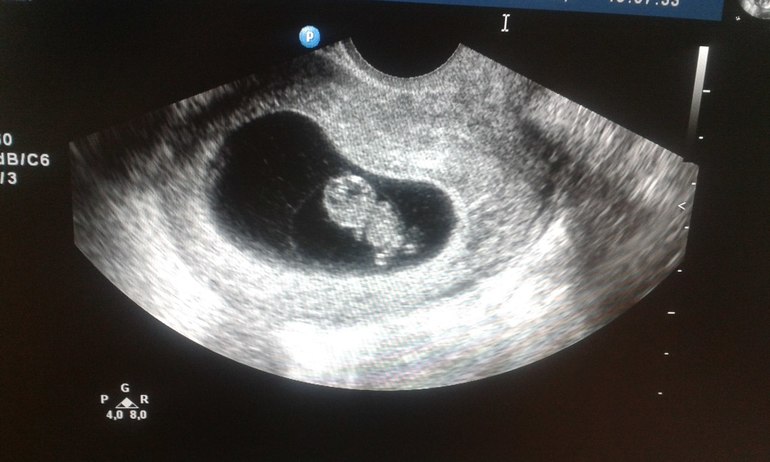

узи

8 недель,2 см от головы до попочки:3 мое маленькое солнышко живет и растет внутри меня! правда поставили угрозу прерывания легкой степени,но мамочка успокоила меня тем,что эту угрозу ставят всем